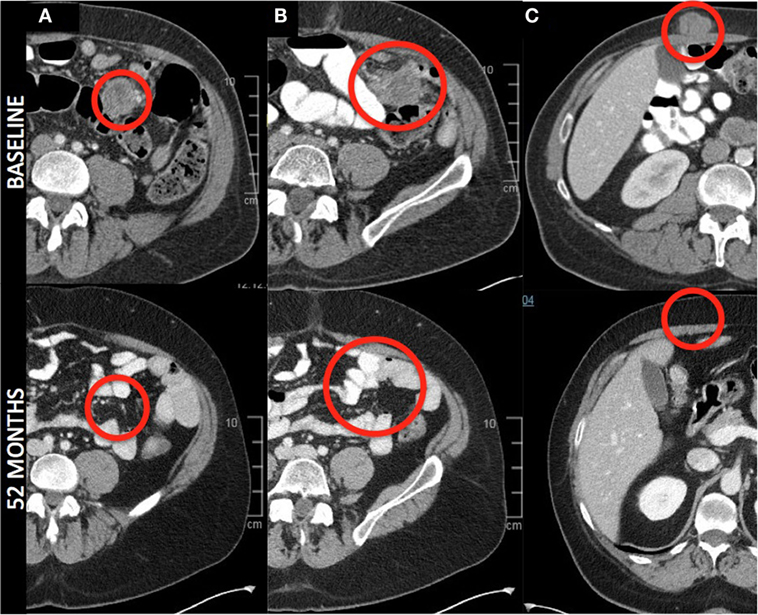

值得一提的是,其中一例完全缓解患者,经TIL+伊匹木单抗联合治疗后,肠系膜(详见下图A、B)和腹壁(详见下图C)的病灶完全消退,所有其他病灶(肝脏和后腹壁,图中未显示)也完全消失。

▲图源“BMJ”,版权归原作者所有,如无意中侵犯了知识产权,请联系我们删除